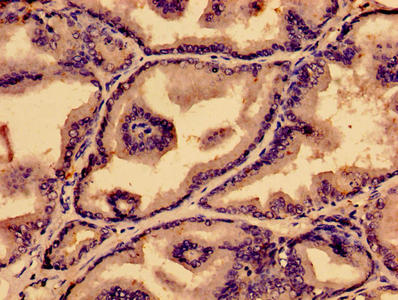

應用范圍:ELISA, IHC, IF

Application Recommended Dilution IHC 1:20-1:200 IF 1:50-1:200 -